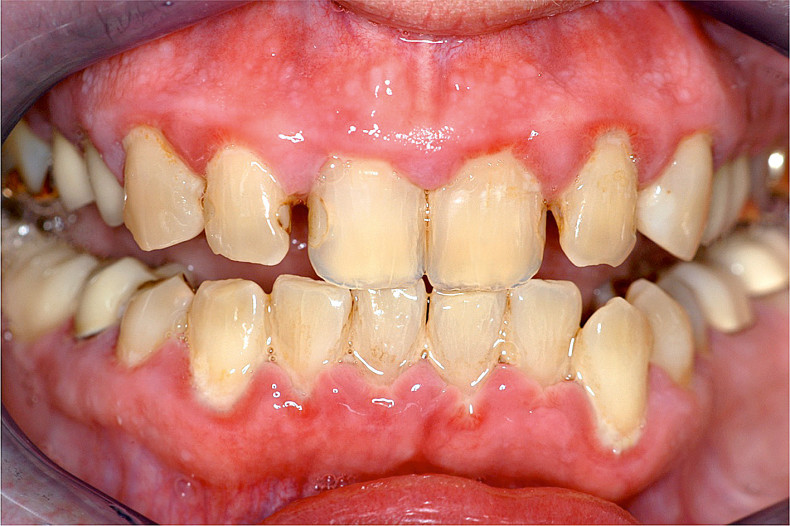

Karies bei Störungen der Speichelsekretion

Zu den charakteristischen Problemen bei Allgemeinerkrankungen (wie Diabetes) oder bestimmten Medikationen (z. B. blutdrucksenkende oder antidepressive Medikamente und bestimmte Psychopharmaka) gehören kariöse Läsionen an Glattflächen sowie die Wurzelkaries. Häufig treten diese in Verbindung mit einer verminderten Speichelsekretion (Xerostomie) auf. Als Folge der fehlenden protektiven Wirkung des Speichels entwickeln sich kariöse Läsionen bei Xerostomiepatienten 15-mal so schnell wie bei gesunden Kontrollpersonen.12 Die rasche Progredienz ist durch die fehlende Pufferkapazität des Speichels zu erklären. Bei nachlassender Remineralisationsfähigkeit und gleichzeitig steigenden Plaqueansammlungen können Demineralisationen vermehrt an sonst wenig kariesanfälligen Flächen entstehen (Abb. 1a–c).13

Gingivale Wucherungen

Als Folge einer antihypertonen Therapie mit Kalziumkanalblockern (Nifedipin), immunsuppressiven Medikamenten (Ciclosporin A) oder bei einer Medikation mit bestimmten Psychopharmaka (trizyklische Antidepressiva, Hypnotika und Sedativa) können bei den dafür empfänglichen Patienten gingivale Veränderungen (Wucherungen) auftreten. In fortgeschrittenen Fällen können diese die Durchführung der Mundhygiene und Therapie von kariösen Defekten in unmittelbarer Nähe der Gingiva erschweren (Abb. 1a und 3a).9

Die im Verlauf einer antihypertonen oder antikonvulsiven Arzneimitteltherapie auftretenden gingivalen Wucherungen werden zunächst konservativ durch eine supra- und subgingivale Belagentfernung behandelt (Abb. 1a–c, 3a und b). Erst wenn nach wiederholten professionellen Zahnreinigungen mit Mundhygieneanweisungen weit ausgedehnte, medikamentös induzierte, gingivale Wucherungen die Kaufunktion beeinträchtigen und eine Zahnpflege erheblich erschweren, ist eine chirurgische Reduktion durch eine Gingivektomie und Gingivoplastik unumgänglich.